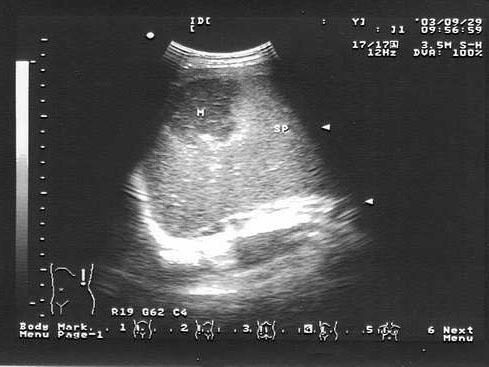

女,现在正在行肺癌放疗治疗。结合超声声像图,诊断为?(?)A.转移性癌B.脾血肿C.脾梗死D.脾脓肿E.脾血管瘤

问题 女,现在正在行肺癌放疗治疗。结合超声声像图,诊断为?(?)

选项 A.转移性癌 B.脾血肿 C.脾梗死 D.脾脓肿 E.脾血管瘤

答案 A